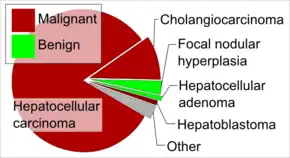

Benign tumors include hemangiomas, liver cysts, hepatic granulomas, and hepatocellular adenomas.[2] Malignant tumors may form within the liver or spread from elsewhere in the body (metastasis).[2] The most common type to form within the liver is a hepatocellular carcinoma, with other types including bile duct cancer and hepatoblastoma.[1][3] They may be discovered on medical imaging and confirmed by tissue biopsy.[1]

Treatment depends on the type of tumor and may vary from none to chemotherapy, surgery, and liver transplant.[1] Benign tumors of the liver are relatively common.[1] Cancerous tumors of the liver are most commonly metastatic.[1] The first descriptions of surgery for liver tumors date from the late 1800s; however, it was not until the 1970s that major advances were made.[4]

Liver tumors are divided into two main groups, benign and cancerous.

- Most cases are metastases from other tumors, frequently of the GI tract (like colon cancer, carcinoid tumors mainly of the appendix, etc.), but also from breast cancer, ovarian cancer, lung cancer, renal cancer, prostate cancer, etc.

- The most frequent, malignant, primary liver cancer is hepatocellular carcinoma (HCC, also named hepatoma, which is a misnomer because adenomas are usually benign).

- More rare primary forms of liver cancer include cholangiocarcinoma, mixed tumors, sarcoma and hepatoblastoma; a rare malignant tumor in children.